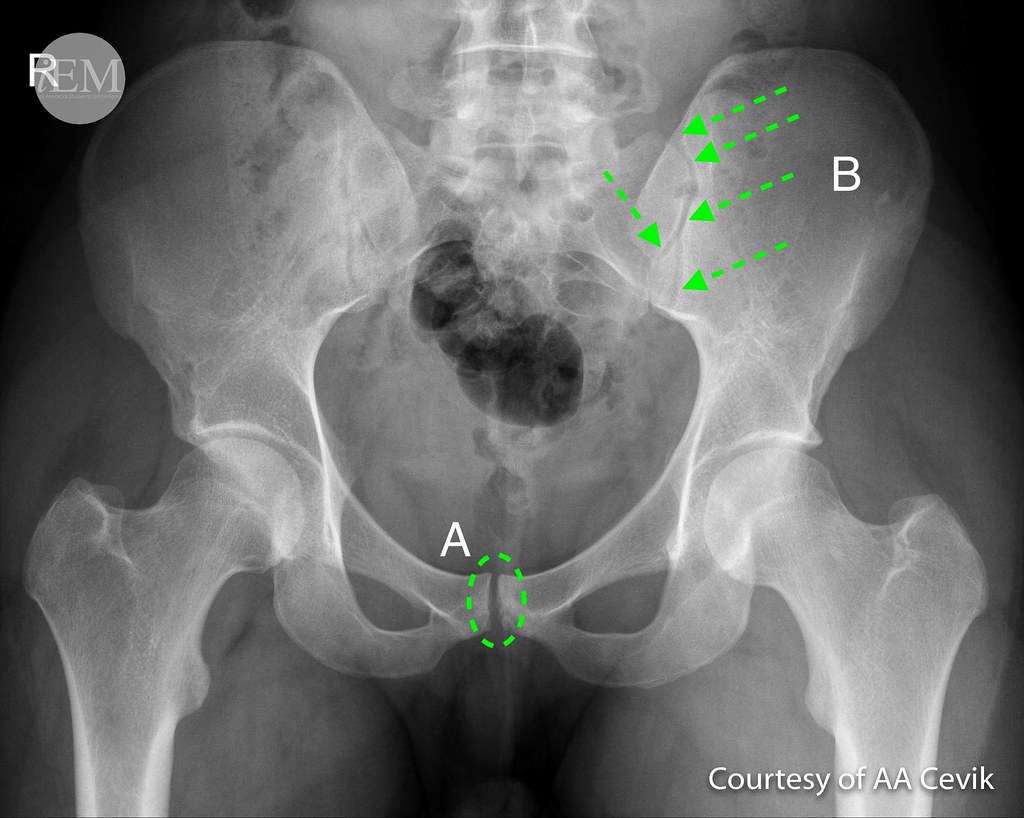

그리고 위 엉치엉덩관절을 Xray 로 찍게 되면

아래 그림의 B 와 같이 나타나게 됩니다.

전에도 진단기준을 말씀드린 적은 있지만 강직척추염의 경우는

방사선학적으로

1) 양측 2도 이상의 천장관절염 또는

2) 단측 3도 또는 4도의 천장관절염 소견이 있어야 하고